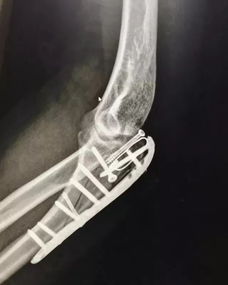

問(wèn)題:什么是粉碎性骨折?粉碎性骨折是什么意思?

粉碎性骨折:多由直接暴力所致,骨折片碎成三塊以上者,稱(chēng)粉碎骨折,多見(jiàn)于成年人,,

《什么是粉碎性骨折》(.unjs)。骨折線(xiàn)呈"T"形或"Y"形時(shí),又稱(chēng)"T"形或"Y"形骨折。